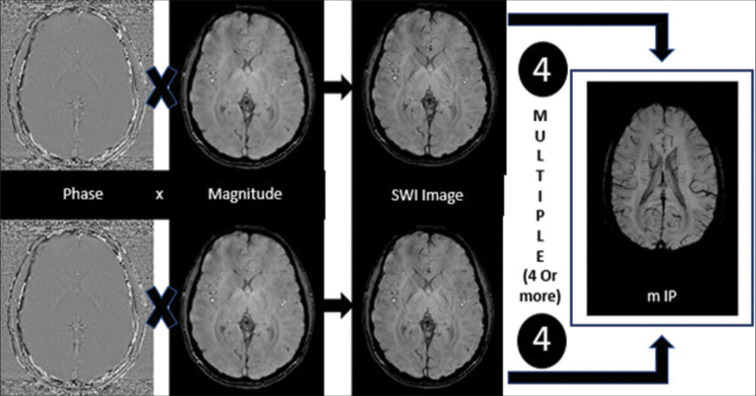

With advances in magnetic resonance imaging (MRI) sequences, there has been increased identification of microbleed/microhemorrhage across different population ages, but more commonly in the older age group. These are defined as focal areas of signal loss on gradient echo MRI sequences (T2* and susceptibility-weighted images), which are usually <5 mm in size representing hemosiderin deposition with wide ranges of etiologies. Susceptibility-weighted imaging (SWI) has become a routine MRI sequence for practices across the globe resulting in better identification of these entities. Over the past decade, there has been a better understanding of the clinical significance of microbleeds including their prognostic value in ischemic and hemorrhagic stroke. Cerebral amyloid angiopathy and hypertension are the two most common causes of microbleeds following peripheral and central pattern, respectively. In the younger age group, microbleeds are more common due to familial conditions or a wide range of hypercoagulable states. This review outlines the pathophysiology, prevalence, and clinical implications of cerebral microhemorrhage along with a brief discussion about the technical considerations of SWI.